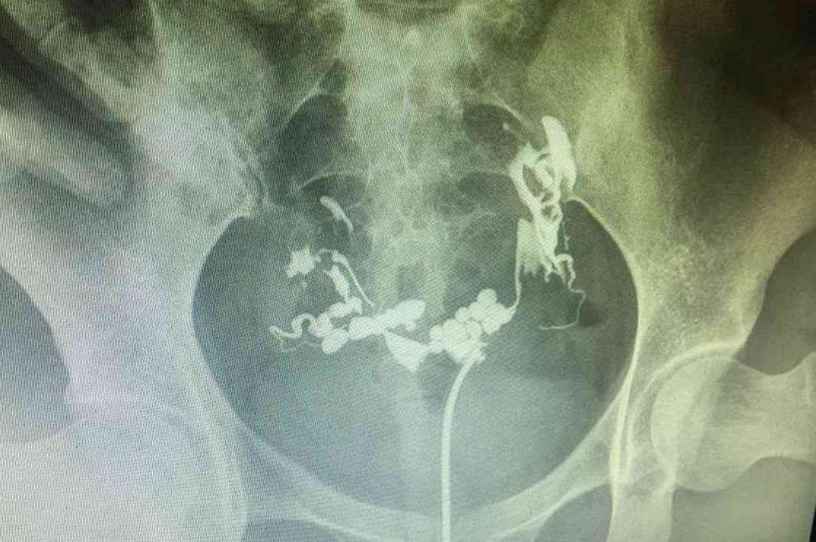

输卵管造影是检查女性输卵管是否通畅的一种重要手段,它可以帮助医生了解输卵管的具体情况,并根据结果制定相应的治疗方案。对于想要怀孕的女性来说,输卵管造影可以帮助她们更好地了解自身情况,并制定合理的备孕计划。那么,输卵管造影后多久可以备孕呢?术后需要注意哪些事项呢?接下来,我们将详细介绍输卵管造影后最佳备孕时间以及术后注意事项。

输卵管造影后最佳备孕时间并没有一个统一的标准,需要根据个体差异、术后恢复情况以及造影结果进行判断。一般来说,如果造影结果显示输卵管通畅,且术后恢复良好,可以尽早开始备孕。建议在术后3-6个月内开始备孕,这段时间可以让身体充分恢复,也能够让受精卵更容易着床。但如果造影结果显示输卵管堵塞或其他问题,则需要在医生指导下进行治疗后再考虑备孕。